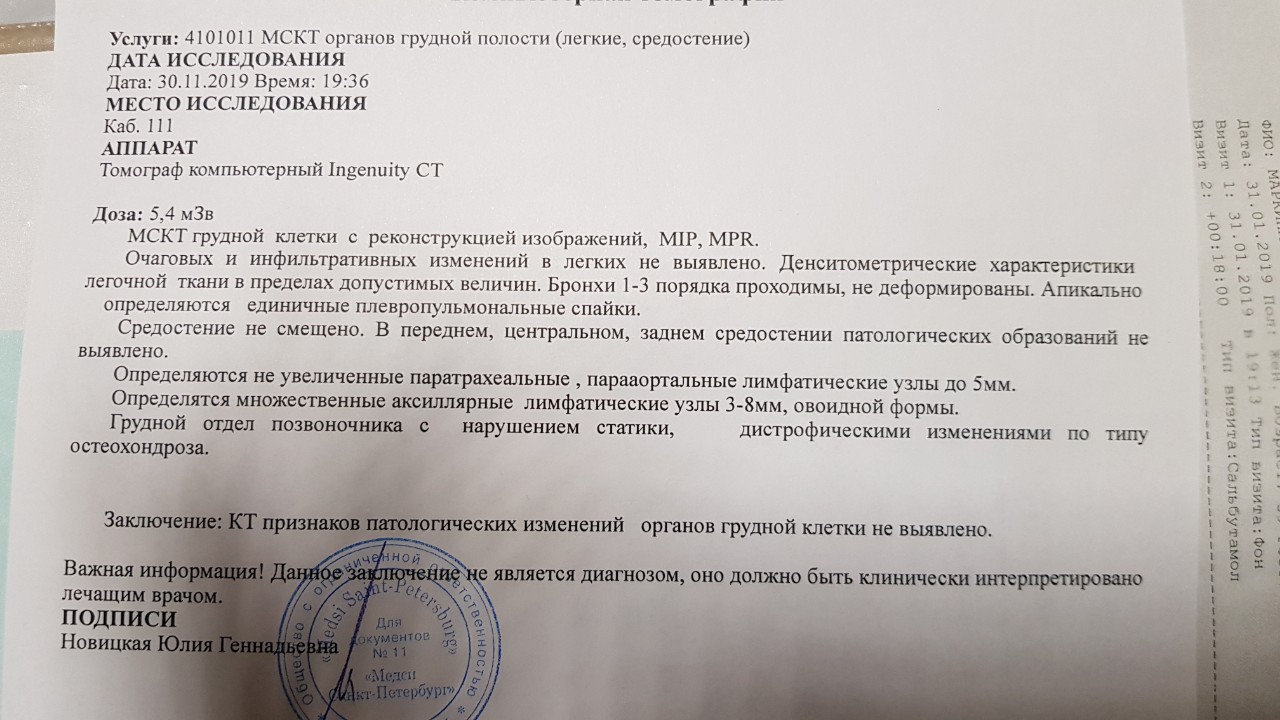

Рентгеновские и МРТ снимки легких